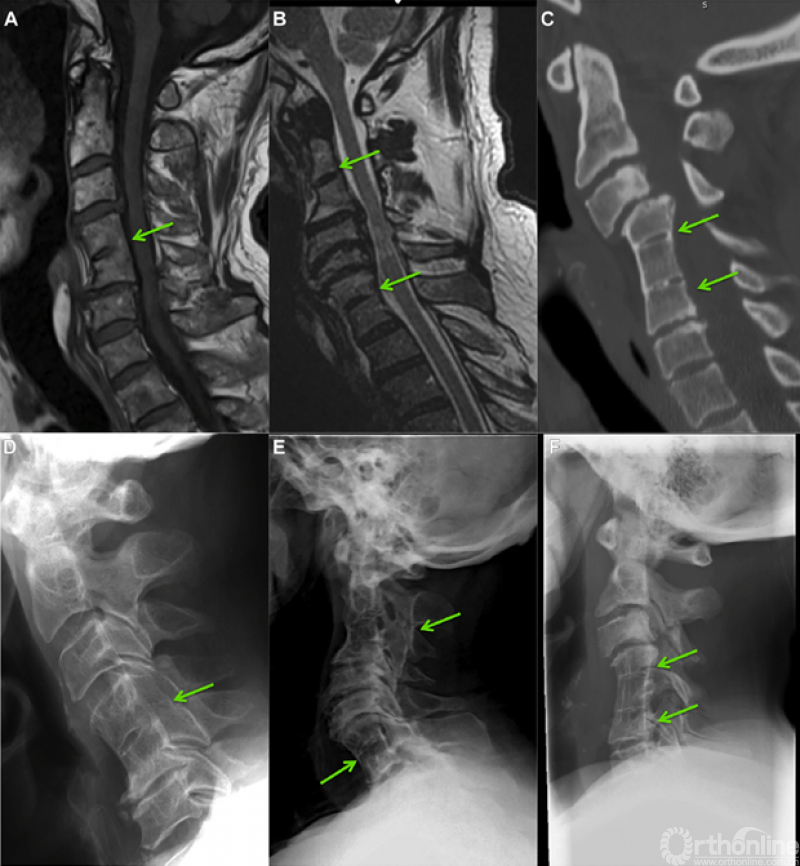

Samartzis分型(图1):I型仅涉及一个先天融合的颈椎节段;II型包含多个不连续的先天融合节段;III型包含多个连续的先天融合节段。

图1.Samartzis分型影像学表现:A和D,I型-单个先天融合的颈椎节段;B和E,II型-多个不连续的先天融合节段;C和F,III型-多个连续的先天融合节段。